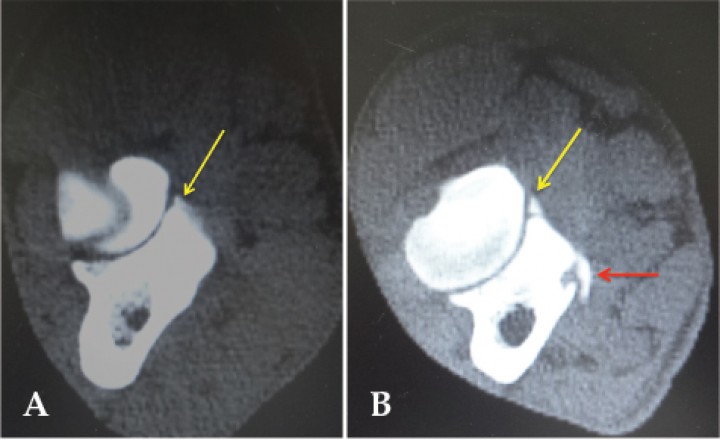

Este es un estudio clínico retrospectivo en el que se incluyen perros diagnosticados de ECM de codo mediante evaluación clínica, estudio radiográfico (Fig. 1), tomografía computarizada (Fig. 2) y evaluación artroscópica (Fig. 3). Dichos pacientes fueron intervenidos mediante la técnica quirúrgica PAUL (Fig. 4) tras la realización de una artroscopia de codo en el mismo acto quirúrgico. Los criterios de inclusión fueron los siguientes: perros que habían sido sometidos a dicho procedimiento quirúrgico en uno o ambos codos y que habían superado un periodo de evolución de cómo mínimo 4 meses. En el caso de intervenirse ambos codos, estas intervenciones debían haberse hecho en dos actos quirúrgicos independientes y con un intervalo mínimo entre ellos de 4 meses.

<div class=\"Basic-Text-Frame\">

<p>Imágenes de tomografía computarizada en plano transversal y ventana de huesos. (A) Se evidencia un fragmento de coronoides medial (flecha amarilla). (B) Imagen de otro paciente en el que además del fragmento craneal (flecha amarilla), se aprecia la deformidad del coronoides y la presencia de un osteofito en la zona medial del coronoides (flecha roja).</p>

Figura 2

Imágenes de tomografía computarizada en plano transversal y ventana de huesos. (A) Se evidencia un fragmento de coronoides medial (flecha amarilla). (B) Imagen de otro paciente en el que además del fragmento craneal (flecha amarilla), se aprecia la deformidad del coronoides y la presencia de un osteofito en la zona medial del coronoides (flecha roja).

Se han utilizado numerosas modalidades de imagen para evaluar esta compleja patología y la severidad de los cambios articulares descritos en la misma;[ Coppieters E, Gielen I, Verhoeven G, Van Vynckt D, Van Ryssen B. Erosion of the medial compartment of the canine elbow: occurrence, diagnosis and currently available treatment options. Vet Comp Orthop Traumatol 2015; 28(1): 9-18. [PubMed] , Cook CR, Cook JL. Diagnostic imaging of canine elbow dysplasia. A review. Vet Surg 2009; 38(2): 144-53. [PubMed] ] sin embargo, a pesar de tratarse de una enfermedad extensamente estudiada, no se ha establecido una aproximación diagnóstica de elección que represente claras ventajas sobre el resto.[ Cook CR, Cook JL. Diagnostic imaging of canine elbow dysplasia. A review. Vet Surg 2009; 38(2): 144-53. [PubMed] ] La radiografía continúa siendo la modalidad de imagen más utilizada, al tratarse de una prueba accesible, económica y segura. No obstante, establecer un diagnóstico definitivo basándose simplemente en el estudio radiográfico de la articulación resulta muy impreciso, y el diagnóstico temprano de la enfermedad continúa siendo un reto.[ Coppieters E, Gielen I, Verhoeven G, Van Vynckt D, Van Ryssen B. Erosion of the medial compartment of the canine elbow: occurrence, diagnosis and currently available treatment options. Vet Comp Orthop Traumatol 2015; 28(1): 9-18. [PubMed] , Houlton J. Advances in canine elbow disease. Vet Surg 2009; 38: 133-134. [PubMed] ] En nuestro caso, todos los animales se sometieron inicialmente a un estudio radiográfico de codo (proyección lateral y cráneo-caudal) que contribuyó, junto con el resto de pruebas realizadas, al diagnóstico definitivo. Para llegar al diagnóstico definitivo de DC, actualmente se recomienda combinar los resultados obtenidos tras realizar una exploración física y ortopédica completa y un estudio radiográfico de la articulación con pruebas de imagen avanzada, a fin de proponer el tratamiento más adecuado en cada caso particular y poder establecer un pronóstico.[ Cook CR, Cook JL. Diagnostic imaging of canine elbow dysplasia. A review. Vet Surg 2009; 38(2): 144-53. [PubMed] ] En nuestro caso, tras la exploración física y ortopédica y el estudio radiográfico de la articulación, todos los animales se sometieron a estudio tomográfico del codo y, en el momento previo a la cirugía, se llevó a cabo en todos los casos la evaluación artroscópica del mismo. Es importante precisar que los autores de este trabajo realizaban también, durante el procedimiento artroscópico, la extracción de los fragmentos existentes en el coronoides, así como el curetaje de las lesiones cartilaginosas existentes, en sintonía con lo referenciado por Tichenor y Millis (2014).[ Tichenor MA, Millis D. Treatment of medial compartment disease of the canine elbow using proximal abduction ulnar osteotomy procedure and a custom kyon plate. Vet Comp Orthp Traumatol 2014; 4: A31-A32. [Kyon] ]